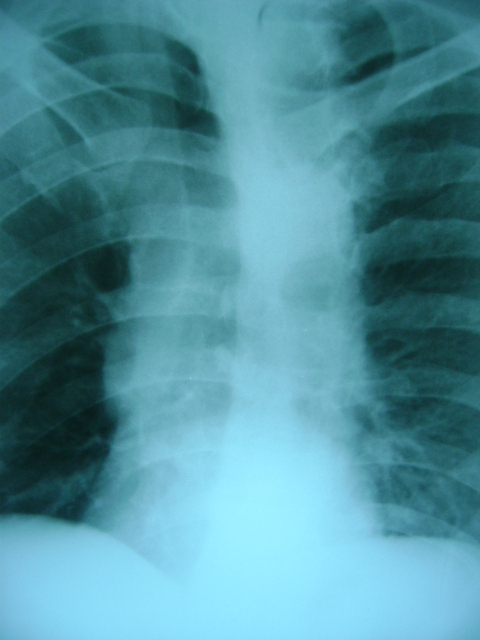

标题: X4564:右位心可能吗

m47y外伤发现

脊柱侧玩畸形,同事怀疑,本人不支持

看起不像哦,脊柱侧弯畸形重叠引起,主动脉弓影在左侧。

胸片类似斜位,心影右旋,应该可否定右位心吧。

轻度左前斜位造成的假象。

不可能为右位心,脊柱侧弯,胸廓畸形所致.

胸廓不对称,脊柱侧弯,导致心脏位置改变,请注意主动脉结,心尖位置,肯定不是右位心.